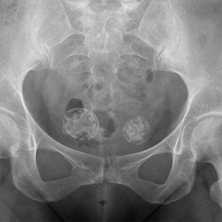

Изменения костных структур малого таза после лучевой терапии

Гинекологический рак является распространенной неоплазией и составляет 10-15% от всех злокачественных новообразований у женщин (1). Задача визуализации до лечения является стадирование злокачественного процесса для дальнейшего планирования терапии и манипуляций. Задача визуализации после лечения (хирургических манипуляций, химиотерапии, лучевой терапии) являются оценка ответа на терапию. Компьютерная томография (КТ) является методом выбора для оценки рецидива рака яичника (2). Магнитно-резонансная томография (МРТ)—в частности, с динамической контрастированием имеет высокую чувствительность (91%) при выявлении рецидивов гинекологического рака (3).

Существуют различные онкологические варианты в гинекологии, в зависимости от локализации, гистологического типа, а также степени и стадии заболевания, поэтому важно, чтобы диагност был готов правильно оценить изображения пациентов после химиотерапии, лучевой терапии или их комбинации, интерпретируя исследование и избегая ошибок в дифференциации нормальной анатомии после лечения и рецидива заболевания.

Химиотерапия чаще используется в качестве неоадъювантного лечения при высокодифференцируемом раке яичников, реже высокодифференцируемом раке шейки матки. Адъювантная химиотерапия используется после операции по поводу рака яичников и рака эндометрия. Первичные химиотерапия и лучевая терапия применяется для лечения распространенного рака шейки матки (2-4 стадии) (4). При эндометриальной карциноме лучевая терапия применяется после хирургического вмешательства у пациентов, у которых патологический процесс распространяется на миометрий или выходит за пределы матки. При раке яичников лучевая терапия рекомендуется только в качестве паллиативного лечения при IV стадии заболевания (4,5).

Примерно у 80% больных костные метастазы локализуются в позвоночнике, костях таза, ребрах, грудине и черепе [5—7]. American Joint Committee on Cancer за 2009 г. приводит данные частоты метастатического поражения костей с учетом локализации (табл. 2).

- Далее по частоте следуют метастазы в костях таза — почти половина всех случаев, типичные локализации — подвздошная и лонные кости.